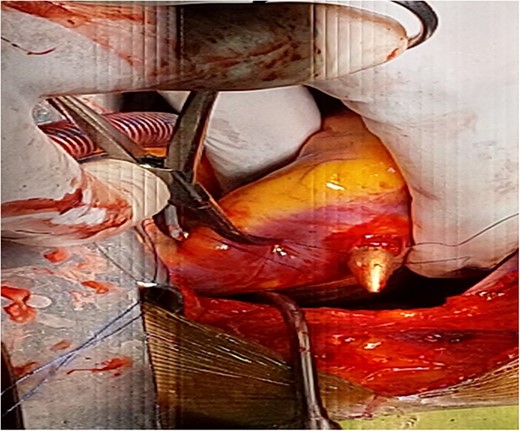

There was a healed scar on the undersurface of the right ventricular wall deep in the myocardium close to the septum and posterior descending artery. The scar was opened, the bullet was extracted along with minimal purulent discharge, which was drained, the cavity was irrigated, and the defect was closed using artificial membrane polytetrafluoroethylene (PTFE) (teflon). Patient was weaned off the CPBP and regular heart beat was achieved. And the patient was extubated on table and was transferred to the cardiac intensive care unit (CICU) with stable condition and normal vital signs. The postoperative course of the patient was uneventful and he stayed a total of 7 days in the hospital after surgery, with 2 days in the CICU and the remaining in the regular ward. He was administered cefepime and vancomycin because of the intraoperatively detected purulent pericardial discharge. His postoperative echocardiography detected normal myocardial activity with no wall motion abnormality and no pericardial effusion. He was discharged on the seventh postoperative day with a stable condition. He was followed as an outpatient and has improved (Figs 4 and 5).

Partially extruded bullet located within the right ventricle wall.